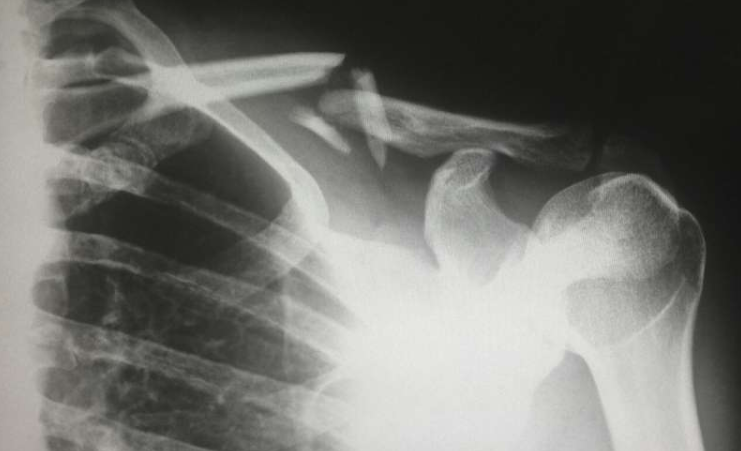

澳大利亚联邦科学与工业研究组织(CSIRO)科学家开发出新型多模态人工智能系统,能够通过结合医学影像与临床数据生成胸部X光诊断报告。该方法采用来自美国医疗机构数据集的4.6万例真实病例进行训练,诊断准确度提升17%,与专业放射科医师的报告一致性显著提高。

研究团队突破传统AI仅依赖影像数据的局限,将急诊部门的生命体征、用药历史和临床记录等多维度信息融入模型训练。项目主要负责人Aaron Nicholson博士表示:"人工智能如同诊断侦探,我们为其提供更多证据线索。当X光影像信息与临床实际情况相结合时,AI诊断的准确性和实用性都得到提升。"